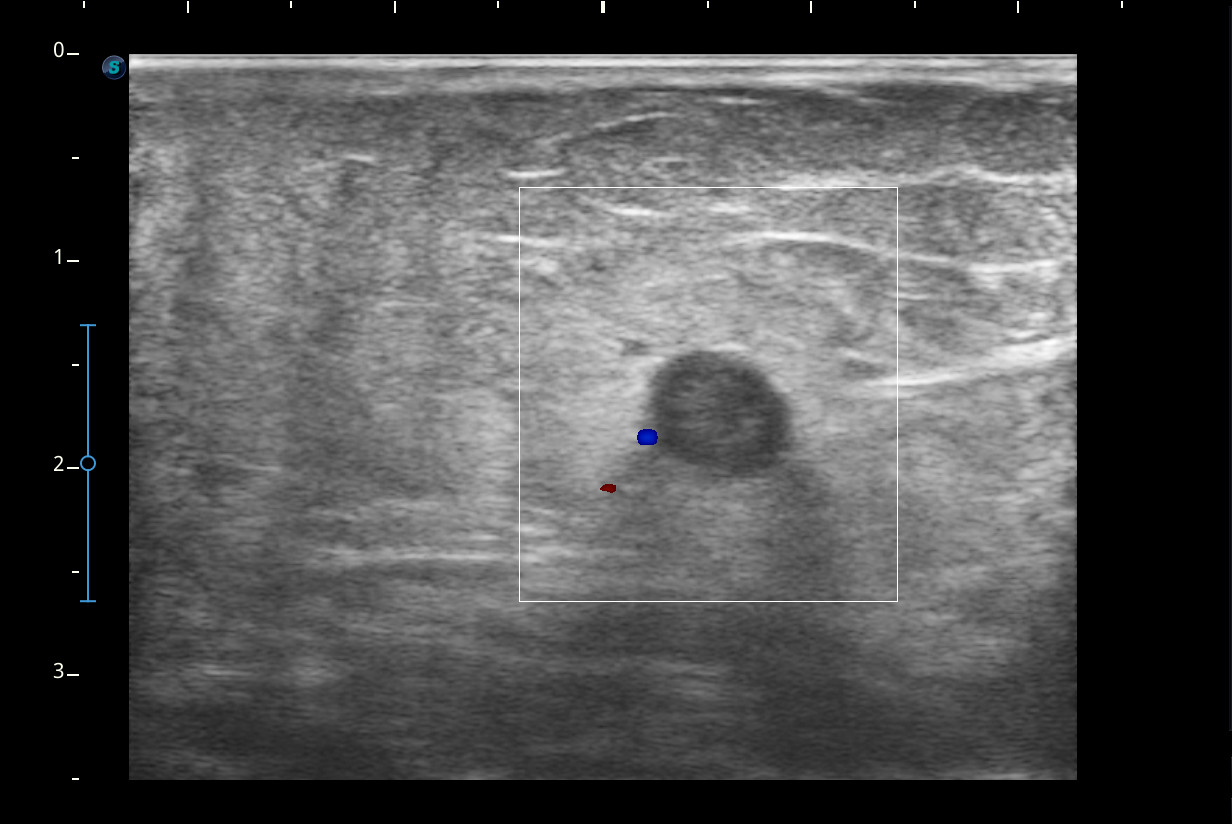

Hallazgos ecográficos

Se visualiza congestión del tejido subcutáneo del brazo y ocupación de la luz de la vena basílica del brazo por un trombo.

Diagnóstico: trombosis venosa de la vena basílica del brazo derecho. Concordancia con el hospital en el segundo tiempo que acude la paciente.

Se remitió a urgencias pero le realizan solamente radiografía del brazo y acude de nuevo a consulta. Nos ponemos en contacto con el SUH y realizan ecografía Doppler.